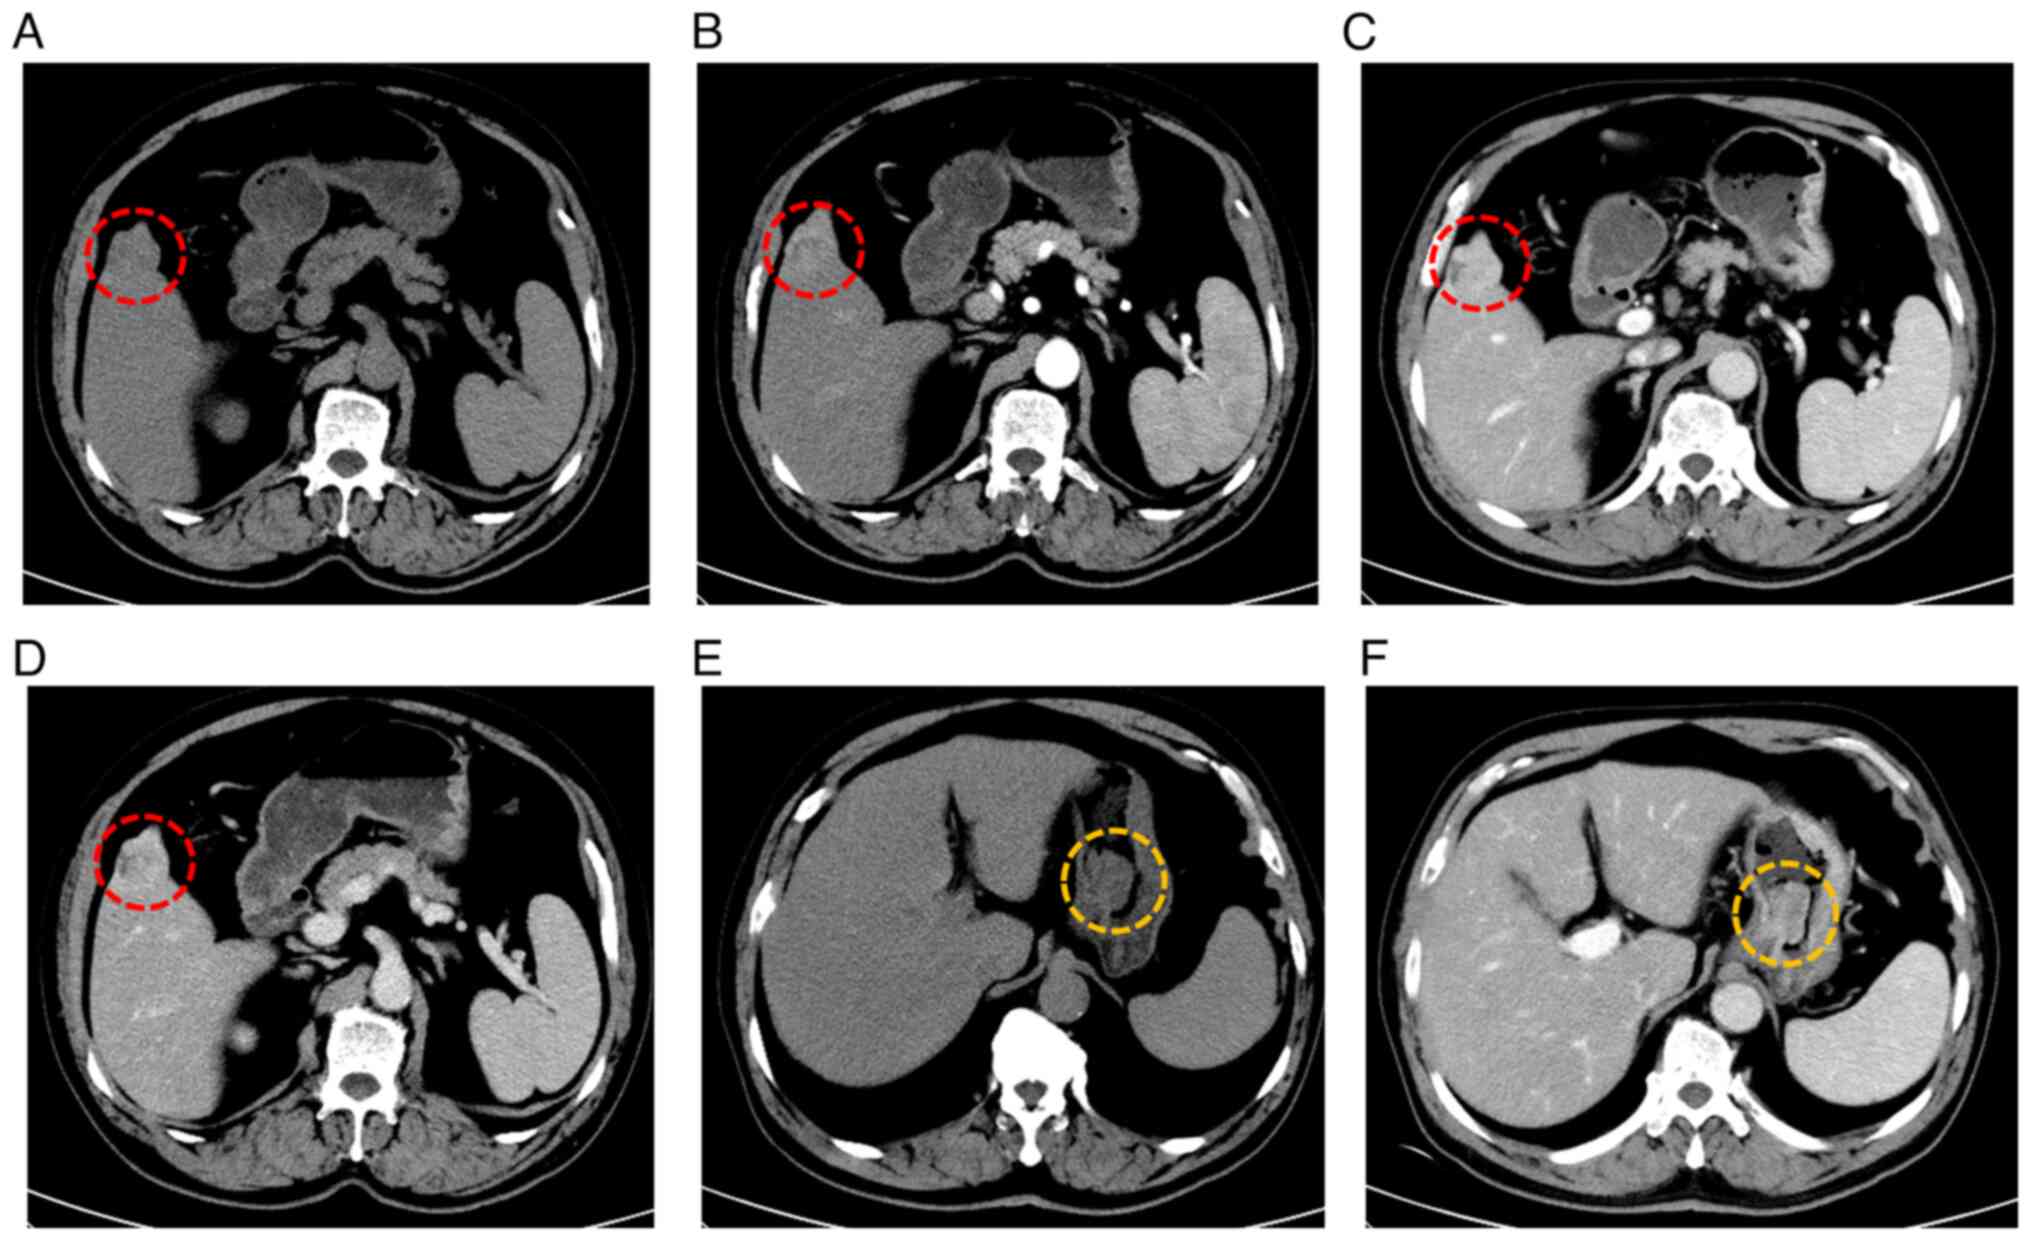

A total abdominal enhanced computed tomography (CT) scan suggested a high likelihood of primary liver cancer and identified a stromal tumor on the lesser curvature of the stomach. Yellow circles highlight a lesion in the gastric fundus (Fig. 1). To further evaluate the gastric soft tissue lesion, gastroscopy was performed, revealing a neoplasm measuring 2.5 cm in diameter with a pedicle, alongside necrosis and ulceration on its surface (Fig. 2). A patchy, rough mucous membrane exhibiting a granular appearance was observed in the gastric angle but not seen under CT images, classified as type IIa + IIc according to the Japanese Research Society for Gastric Cancer (Fig. 3) (11). Narrow band imaging revealed local irregularities in glandular ducts and neovascularization. Pathological examination indicated high-grade dysplasia of the mucosal glandular epithelium, accompanied by chronic active inflammation, surface necrosis and erosion. Given the presence of tumors in both the liver and gastric angle, it remained uncertain whether the patient had synchronous primary tumors or a gastric tumor with liver metastasis. To clarify the diagnosis, an enhanced MRI with a liver-specific contrast agent (disodium gadoxelate) was conducted, confirming primary liver cancer in the S5 segment and early gastric cancer in the gastric angle (Fig. 4).

Figure 1.

Total abdominal enhanced CT revealed space-occupying lesions in the stomach and liver. (A) Plain scan, (B) arterial phase, (C) portal phase and (D) delayed phase CT images of the liver segment 5 lesion. Red circles indicate a liver lesion in segment 5. (E) Plain and (F) enhanced CT scans show a protruding lesion that is of similar size to other lesions demonstrating progressive enhancement. Yellow circles highlight a lesion in the gastric fundus. CT, computed tomography.